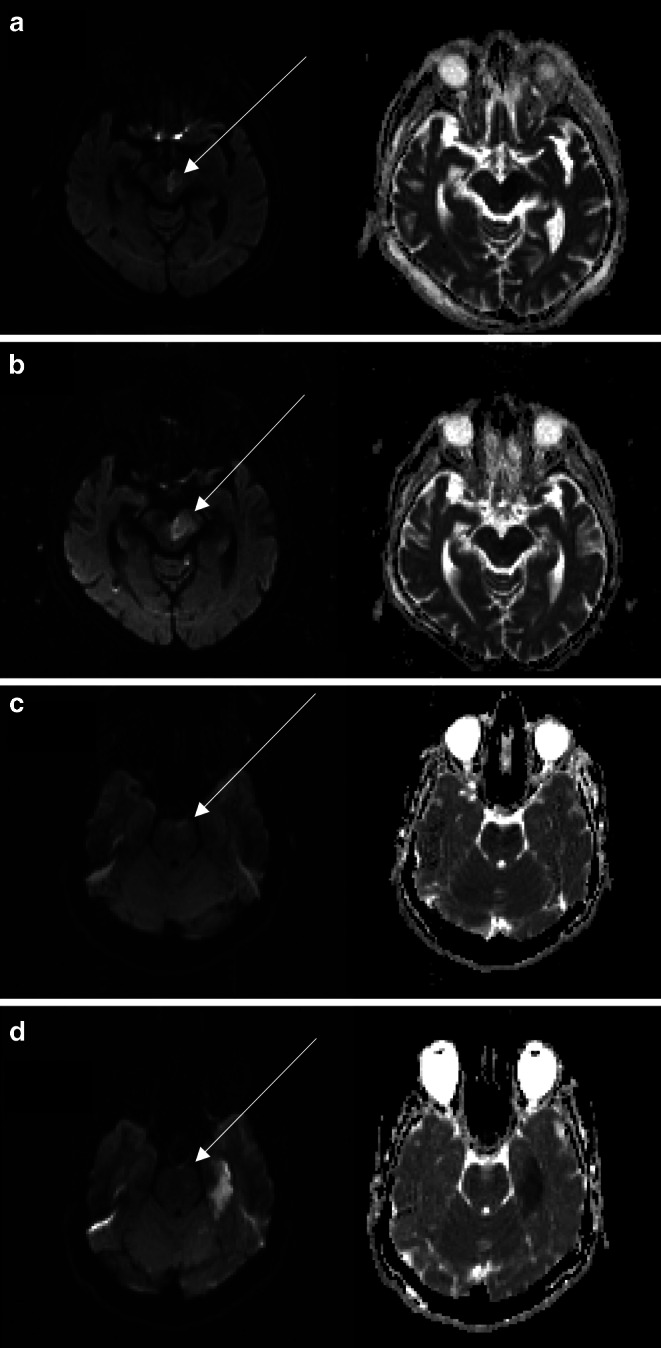

目的:弥散加权成像(DWI)表征急性缺血性脑卒中的梗死核心。DWI可逆性是一种影响脑白质小区域的前循环的现象。本研究旨在明确基底动脉闭塞(BAO)再通成功后后循环DWI可逆性及其对患者预后的影响。方法:回顾性分析2015年1月至2022年12月对脑卒中患者进行分析的两个三级脑卒中中心。纳入标准为急性脑卒中治疗前后MRI及BAO再通成功。脑区被定义为脑干、小脑和幕上脑由后循环供应的脑区。在单因素分析中对这些区域进行比较。其次,比较DWI可逆性患者和无DWI可逆性患者的预后,单因素分析以预后良好为主要终点(mRS 90d 0 ~ 2)。结果:总共有5/28的纳入患者(21.74%)显示DWI可逆性,DWI可逆性仅发生在脑干。与小脑或幕上梗死相比,脑干梗死的总体范围与患者预后的相关性更好(Spearman ρ = 0.757;p 结论:急性脑卒中合并BAO患者脑干DWI限制可逆性明显。在这项研究中,与小脑或幕上梗死相比,患者预后与脑干梗死的范围相关性更强。

Results: In total, 5/28 of included patients (21.74%) showed DWI reversibility, which was exclusively found in the brainstem. The overall extent of brainstem infarction correlated better with patient outcome compared to cerebellar or supratentorial infarction (Spearman's ρ = 0.757; p < 0.001). Good outcome was more frequent in patients with DWI reversibility compared to those without (mRS 0-2, DWI+ n = 4, 80% vs. DWI- n = 6, 26%, p = 0.023).

Conclusion: DWI restriction reversibility was observed in the brainstem of acute stroke patients with BAO. In this study, patient outcome correlates stronger with the extent of brainstem infarction compared to cerebellar or supratentorial infarction.